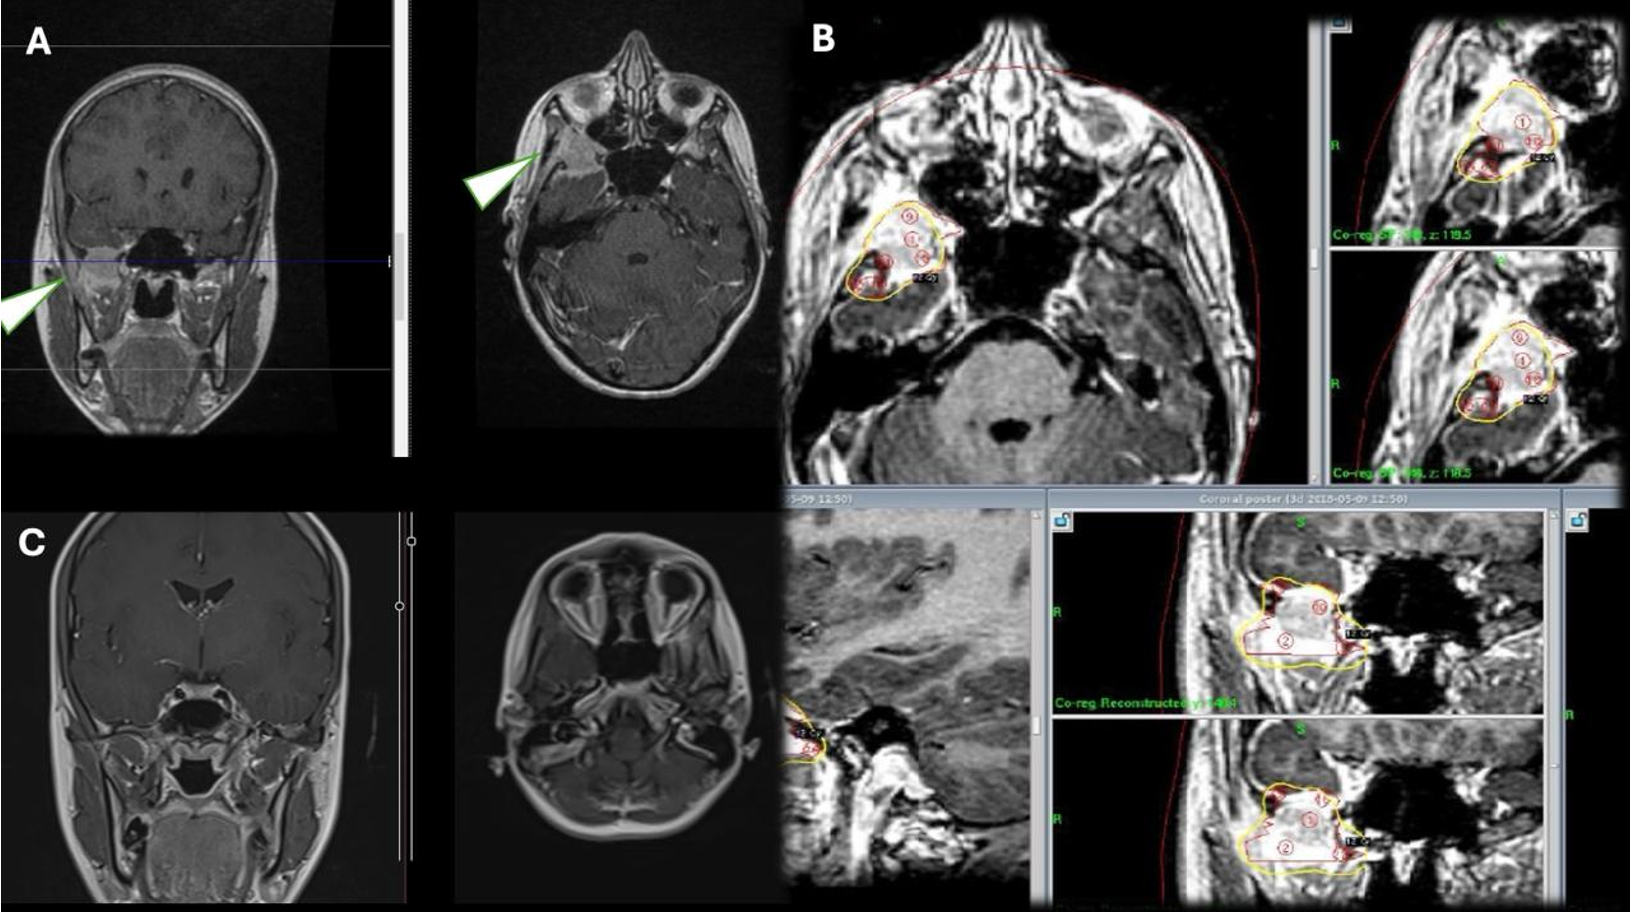

Meningiom saptanan üç hastanın ilki 14 yaşında Nörofibromatozis Tip 2 (NF – 2) tanısı olan erkek hastanın kavernöz sinüs yerleşimli kitlesine GKRC uygulanmış olup 11 aylık takibinde lezyon stabil kalmıştır. İkinci hasta olan 8 yaşında kız hastanın kavernöz sinüs yerleşimli cerrahi sonrası rezidü olan kitlesine (Psammomatöz meningiom (DSÖ Derece 1)) yönelik GKRC uygulandı ve 12 aylık takipte lezyonun küçüldüğü gözlenmiştir. Üçüncü hasta olan 17 yaşındaki kız hastanın orta fossa anteriyor kesiminde yerleşen meningioma 12 Gy dozunda tedavi uygulandı (Şekil 3). 48 aylık takipte lezyon izlenmedi.

Kraniofarengiom tanılı iki erkek hastadan ilki 7 yaşında olup cerrahi patolojisi adamantinamatöz kraniofarengiom olarak sonuçlanmıştır. Önce transkraniyal, 4 ay sonra transsfenoidal yolla cerrahi yapılan hastaya ilk ameliyatının 6. ayında rezidü kitle nedeniyle GKRC uygulandı. 9. ayında kitlenin kistik komponenti için cerrahi yapılan hastanın 12 aylık takibi sonucunda kitlenin kaybolduğu görüldü. Diğeri hasta ise 6 yaşında olup transsfenoidal yolla 2 kez ameliyat edilmiş ve rezidü kitlesine yönelik hacim bölünerek 2 seans GKRC yapıldı (Şekil 4). 37 aylık takipte kitlenin kaybolduğu tespit edilmiştir.